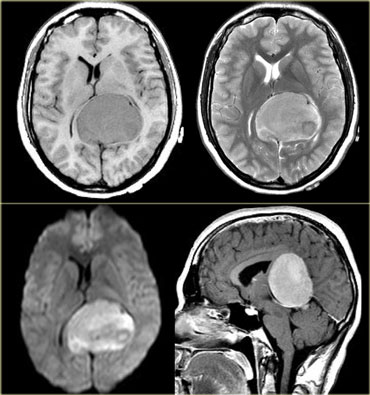

Intraventricular

Common intraventricular Tumors are listed in the table on the left.

On the left a tumor located in the 3rd ventricle.

The tumor contains calcifications.

The diagnosis is a giant cell astrocytoma.

4th ventricle

In children tumors in the 4th ventricle are very common.

Astrocytomas are the most common followed by medulloblastomas (or PNET-MB), ependymomas and brainstem gliomas with a dorsal exophytic component.

In adults tumors in the 4th ventricle are uncommon.

Metastases are most frequently seen, followed by hemangioblastomas, choroid plexus papillomas and dermoid and epidermoid cysts.